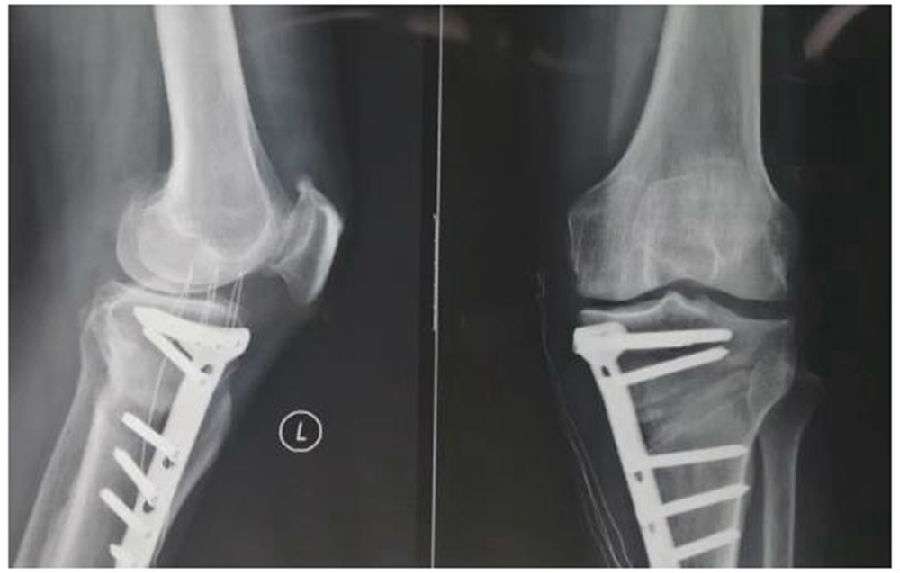

2、处理

(1)如果在手术台上,或是刚做完手术就发现矫正不良问题,此时比较简单。需要先跟患者进行沟通,在手术中直接将远端4颗螺钉卸下来,调整好力线后重新打入即可。但是注意要把远端单皮质螺钉换成双皮质螺钉。

(2)如果患者已经达到初始愈合,此时如果出现过度外翻,需要在内侧重新做内侧闭合楔。

(3)如果做完手术时间较长,出现过度矫正或矫正不足时,需要重新做力线分析,看一看力线在哪个方向可以再进行调整。胫骨侧有调整余地,就在胫骨侧进行调整;股骨侧需要调整,就在股骨侧进行调整。